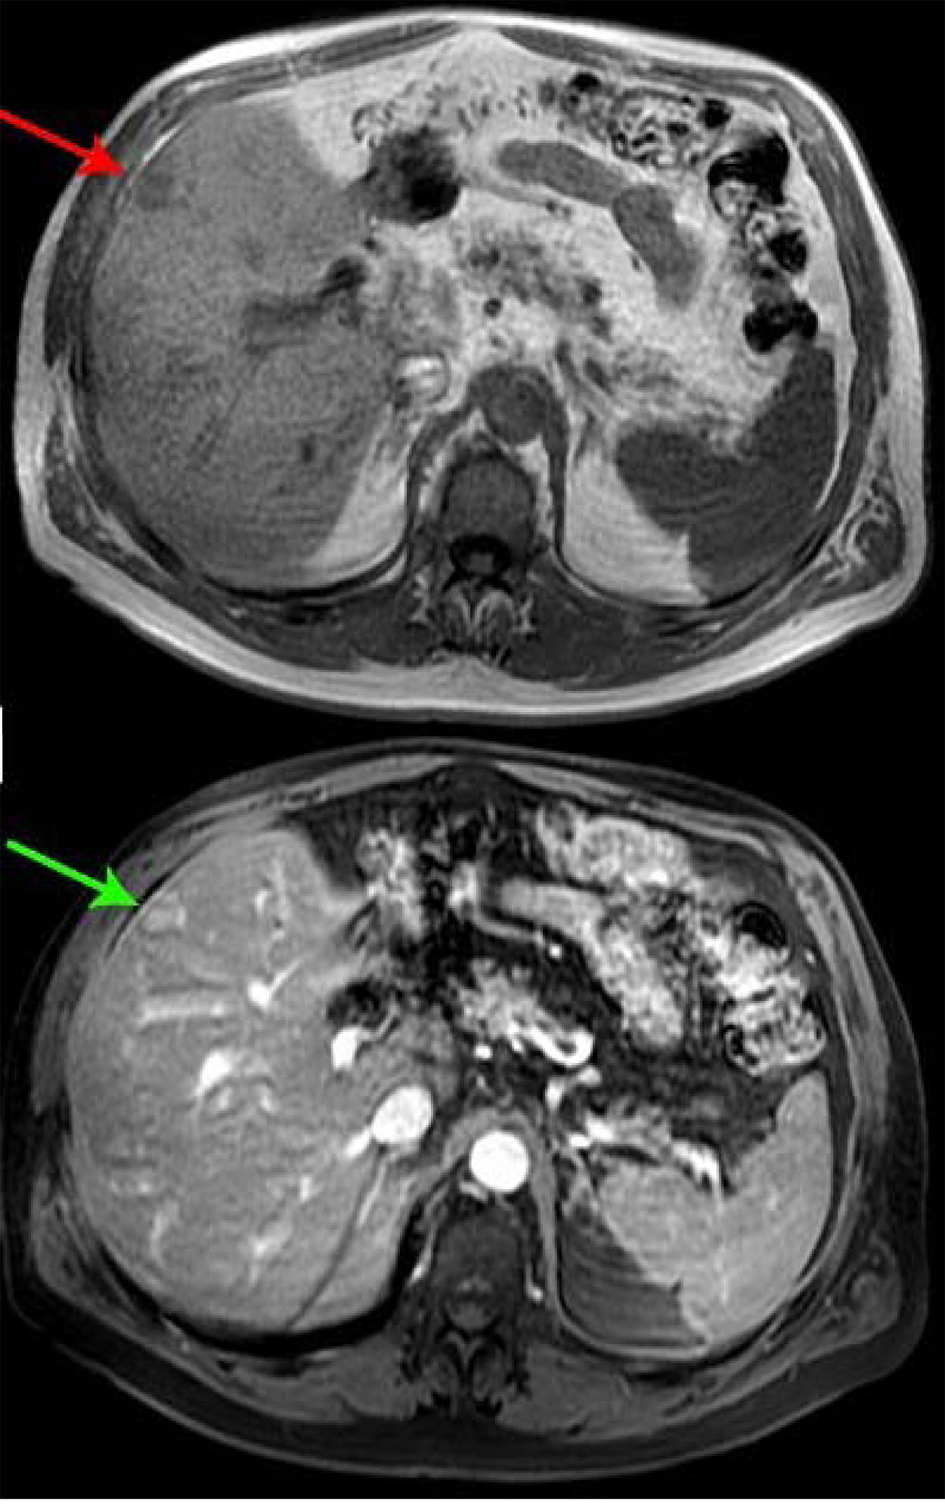

A 66-year-old male presented with small bowel obstruction due to a cecal mass requiring exploratory laparotomy. Pathology revealed a well-differentiated neuroendocrine tumor with regional nodal metastases (Figure 1 shows small intestinal tumor in low power view (a), high power view (b), chromogranin stain (c), synaptophysin stain (d)). Eight months after surgery the patient presented with persistent diarrhea. Indium 111 octreotide scintigraphy (OctreoScan®) revealed increased activity in the left leg and right lobe of the liver (Figure 2 with green arrow shows metastasis to the liver, red arrow showing metastasis to left thigh). An abdominal MRI demonstrated a 2 cm subcapsular lesion at the right hepatic lobe (Fig. 3) and CT scan demonstrated an enhancing soft tissue mass in the left vastus intermedius muscle measuring 30 × 17 × 16 mm (Fig. 4). Biopsy of the left thigh lesion showed metastatic well-differentiated neuroendocrine tumor (Fig. 5). Subsequent CT scan demonstrated increase in the size of the liver and muscular lesions and Sandostatin® LAR was initiated.

![]() Click for large image | Figure 3. Abdominal MRI. |